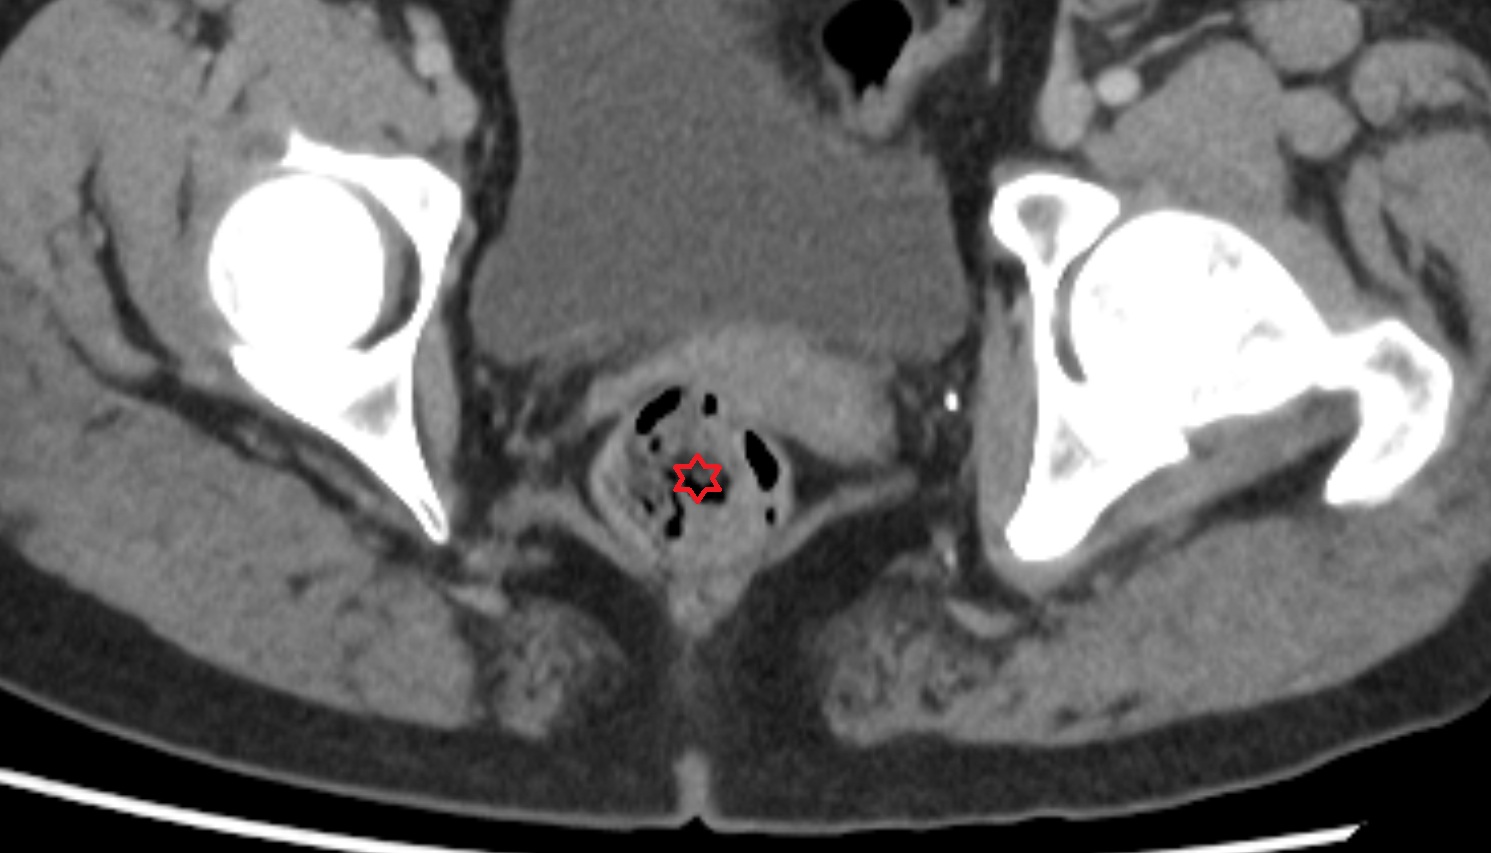

- Peripheral zone of prostate

- Anterior Fibromuscular Stroma of prostate

- Central zone of prostate

- Transitional zone of prostate

- Membranous urethra

- Prostatic urethra

- Penile urethra